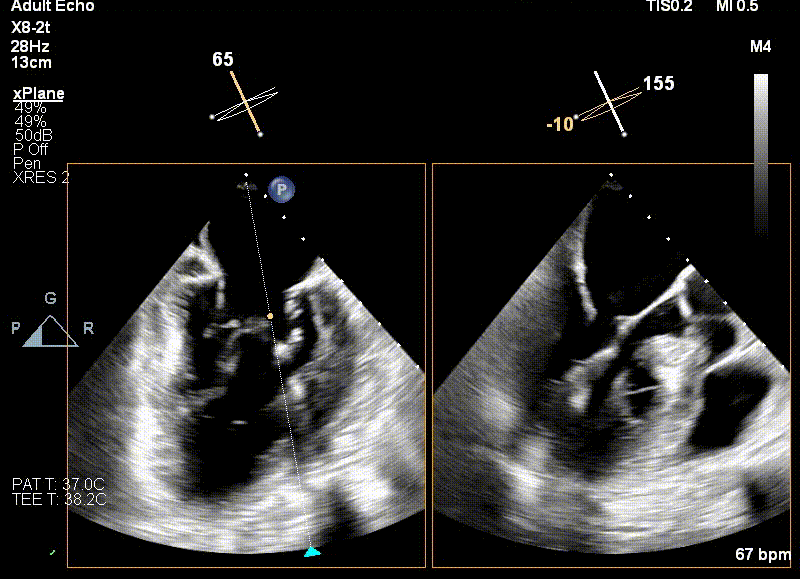

术前TEE评估

原发性MR,交界C1区脱垂,反流程度4+;二尖瓣瓣口面积3.88cm²,平均跨瓣压差2mmHg;二尖瓣前叶(A1)长度16.2mm,二尖瓣后叶长度(P1)长度9.9mm,脱垂高度6mm。

王建安教授调整二尖瓣夹轨迹和方向,使其轨迹垂直于二尖瓣环平面且指向心尖,定位于二尖瓣C1区且指向1-7点钟方位。

经食道超声引导后,王建安教授将二尖瓣夹NTR夹取C1区瓣叶,准确成功捕获C1前叶和后叶反流最严重区域,并予夹合。使二尖瓣在收缩期由大的单孔变成一大一小的双孔,显著减少了二尖瓣反流。